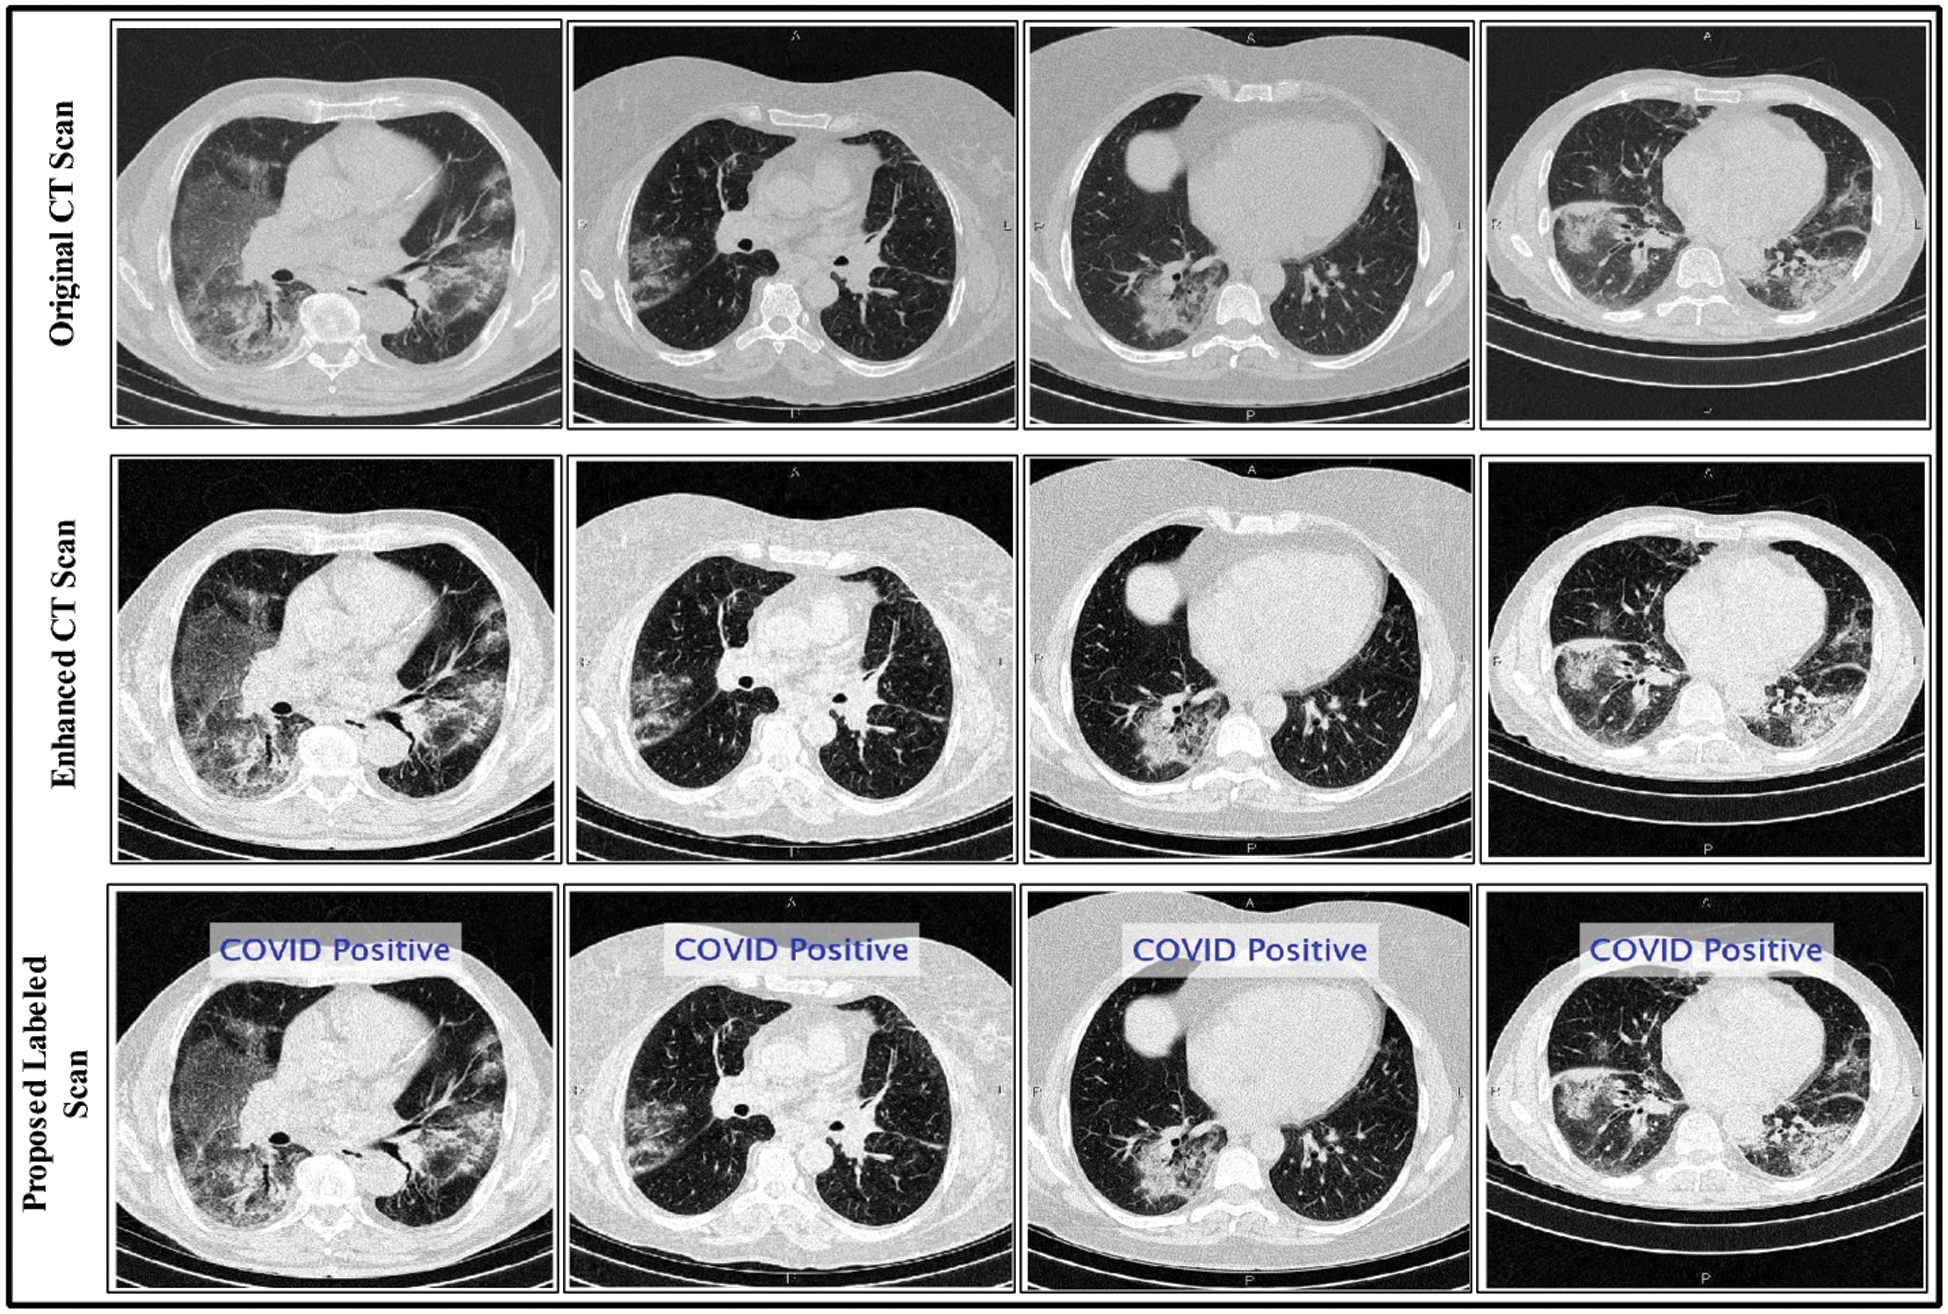

are used in different combinations for classification, regression, sparse coding, feature learning, and clustering. The output of the ELM is in the form of labeled images and numerical results, as shown in Fig. 5; numerical results are presented in Section 4. In this study, we compared the ELM performance to well-known classification techniques to demonstrate its effectiveness in the proposed scheme.

In this section, the results of the proposed method are presented in the form of numerical values and plots. Details of the data set are given in Section 3.1. A total of 9,000 CT images were used, including 5,000 positive COVID-19 images and 4,000 healthy images. Of all CT images, 60% were used for the proposed model training and 40% were used to test the technique. Tab. 1 lists the experimental parameters. Fig. 1 shows the sequence of steps in the proposed method; the results of each step were computed to emphasize their importance. The computed results include the following: (i) An average pool layer extracted feature evaluation; (ii) FC layer feature evaluation; (iii) FA-based optimized average pool layer feature evaluation; (iv) FA-based optimized FC layer feature evaluation; and (v) fusion of both optimized feature vectors. A 10-fold cross-validation was conducted for training as well as testing of the proposed system. The ELM was used as a key classifier for feature classification; its performance was compared to that of other techniques such as naïve Bayes, linear support vector machine (LSVM), weighted k-nearest neighbor (KNN), and ensemble tree (bagging). In the simulation process, MATLAB 2019b was used on Desktop Compute (16 GB RAM; 256 SSD). In addition, an 8 GB graphics card was used to minimize the computation time.

Figure 5: Proposed method labeled results